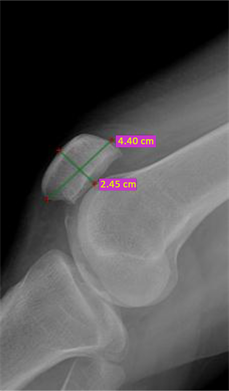

For male, average weight was 63 ± 13 kg, height was 168 ± 10 cm and average BMI was 22 ± 5.17 kg/m2. For female average weight was 65 ± 12 kg, height was 167 ± 10 cm and average BMI was 23 ± 5.3 kg/m2. Average FML was 62.6 ± 7.45 mm in male and 59.1 ± 5.79 mm in female participants. Average FAP was 70.6 ± 1.22 mm in male and 66.9 ± 3.93 mm in female. Average TML in male was 85.6 ± 1.27 mm and 79.1 ± 0.8 was in female. Average TAP was 60.1 ± 4.87 mm in male and 55.7 ± 4.96 in female. Average PAP was 22.5 ± 2.83 mm in male and 23.8 ± 2.43 mm in female. Average PML was 50.2 ± 1.45 in male and 46.8 ± 4.09 mm in female (Figure 3, Figure 4).

Figure 4. Lateral image of patellar X-ray (PML-44 mm, PAP-24.5 mm).

dimensions of male and female participants. As a result of the measurements, there was statistically significant difference in male and female patella (P < 0.002).